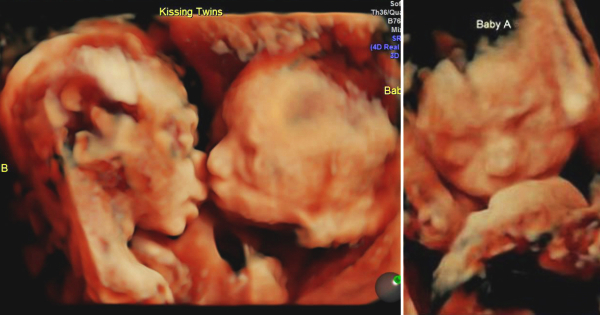

Родители споделија снимки од ултразвук за да ја покажат специјалната врска меѓу нивните неродени близначки. На снимките, двете бебиња се „бакнуваат“ во утробата на нивната мајка.

Кариса Гил била во 25-тата недела од бременоста кога со сопругот Ренди ги виделе своите идни ќерки како си разменуваат „бакнежи“ за време на прегледот со ултразвук. Кариса вели дека не ни помислувала дека близначките Изабела и Кејли се толку блиску една до друга, па моментот бил многу посебен за неа.

Кариса на Instagram сподели и друга фотографија на која едното бебе го „бакнува“ другото на образот. „Изабела ја бакнува својата сестричка Кејли на образот“ – напиша таа.